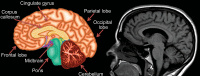

Neurodegenerative diseases are a devastating group of disorders that can be difficult to accurately diagnose. Although these disorders are difficult to manage owing to relatively limited treatment options, an early and correct diagnosis can help with managing symptoms and coping with the later stages of these disease processes. Both anatomic structural imaging and physiologic molecular imaging have evolved to a state in which these neurodegenerative processes can be identified relatively early with high accuracy. To determine the underlying disease, the radiologist should understand the different distributions and pathophysiologic processes involved. High-spatial-resolution MRI allows detection of subtle morphologic changes, as well as potential complications and alternate diagnoses, while molecular imaging allows visualization of altered function or abnormal increased or decreased concentration of disease-specific markers. These methodologies are complementary. Appropriate workup and interpretation of diagnostic studies require an integrated, multimodality, multidisciplinary approach. This article reviews the protocols and findings at MRI and nuclear medicine imaging, including with the use of flurodeoxyglucose, amyloid tracers, and dopaminergic transporter imaging (ioflupane). The pathophysiology of some of the major neurodegenerative processes and their clinical presentations are also reviewed; this information is critical to understand how these imaging modalities work, and it aids in the integration of clinical data to help synthesize a final diagnosis. Radiologists and nuclear medicine physicians aiming to include the evaluation of neurodegenerative diseases in their practice should be aware of and familiar with the multiple imaging modalities available and how using these modalities is essential in the multidisciplinary management of patients with neurodegenerative diseases.©RSNA, 2020.